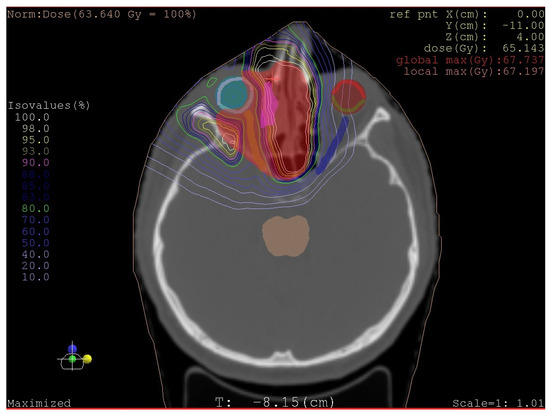

- Radiotherapy: beam therapy (photon, proton, or isotope) depends on staging, including grading, histological type of sarcoma, and the radicality of surgery when performed.